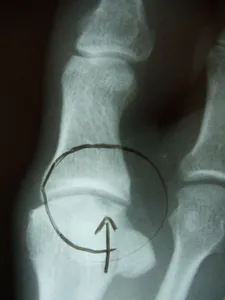

• X-rays are taken to evaluate the joint surface.

• If an x-ray is positive for an osteochondral lesion, then a CT scan may be necessary to help stage the lesion (I through IV) and evaluate the size of the lesion.